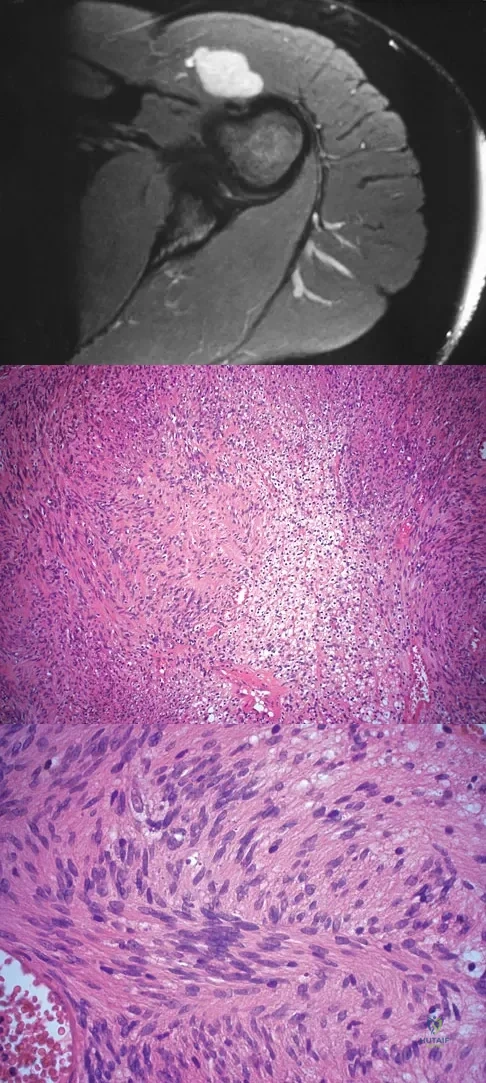

A 28-year-old woman has left shoulder pain and a tender soft-tissue mass. Based on the MRI scan and biopsy specimens shown in Figures 74a through 74c, what is the most likely diagnosis?

Explanation